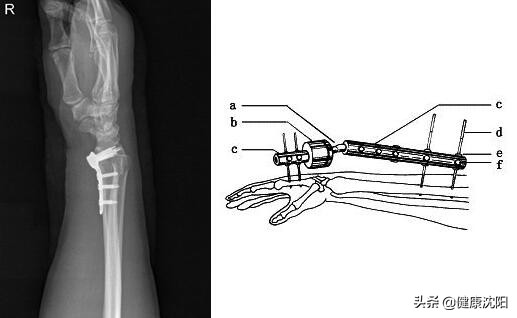

有时候,骨折端发生明显的移位,使用闭合复位、小夹板固定很难矫正过来,而且很有可能会影响到日后手臂的活动功能,此时骨科医生将会建议进行手术治疗。根据骨折类型,可以选择合适的手术方法使之正确复位以及愈合。主要的治疗方法有:钢板螺钉固定、外固定支架(固定在患肢部位外边的一个稳定支架,维持骨折端良好对位,可以使之愈合)等。